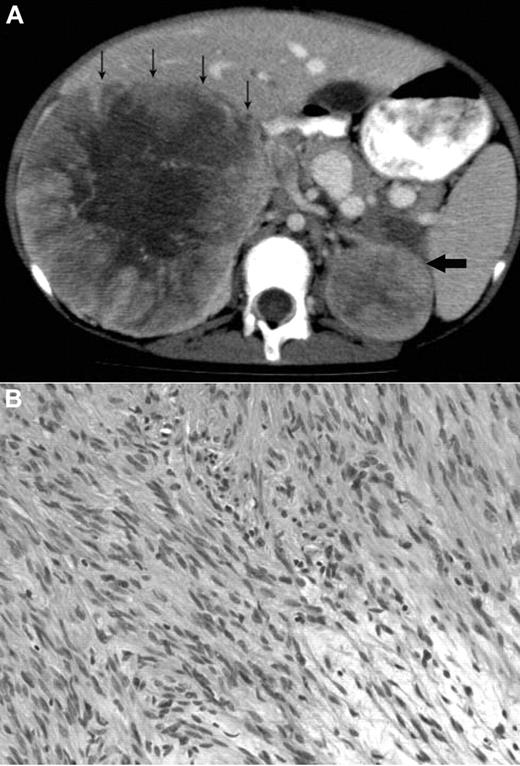

Radiologic and histologic findings. (A) Axial CT view of the upper abdomen after intravenous contrast injection and oral contrast administration: Large solid mass in the right suprarenal region with faint central calcification and central stellar hypodensity. Small arrows indicate the anterior border of this mass. The smaller more homogeneous solid lesion in the left suprarenal region is indicated by one large arrow. The right-sided lesion displaces the inferior vena cava anteriorly and medially, and there is visibility of an intracaval defect corresponding to a clot. (B) H&E stain showing elongated spindle cells arranged in a storiform pattern admixed with scattered chronic inflammatory cells (original magnification ×400). The images were captured digitally through a Nikion Eclipse i80 microscope (Nikon) with a 40×/0.75 objective at room temperature without flourochromes. The camera was a Pixelink PL-SW Microscopy (Canimpex Enterprise Ltd) with acquisition software of Pixelink Capture SE Version 4 software for Windows XP (Canimpex Enterprise Ltd). No subsequent image reprocessing occurred.

The microscopic findings in the left and right adrenal tumors were diagnostic of EBV-SMTs7,8 (Figure 1B). Elongated spindle cells with eosinophilic cytoplasm were present along with inflammatory cells, including lymphocytes and histiocytes. The endothelial cell lining was in a hemangiopericytoma-like pattern. Immunoperoxidase staining demonstrated positive vimetin, smooth muscle actin, and desmin, all specific findings in SMTs.8 Lastly, in situ hybridization for EBV early RNAs produced strong and diffuse reactivity in addition to positive nuclear staining of EBV early RNAs. An initial tumor biopsy showed a translocation t(4;21) (q21:q11.2) but was not replicated in subsequent cytogenetic cultures and is of uncertain significance. Constitutional chromosomes were normal.